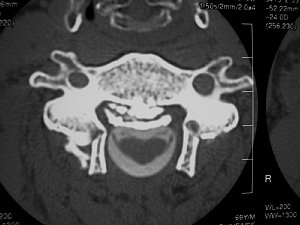

難病の頚椎後縦靱帯骨化症の手術前 |

手術後 | ||